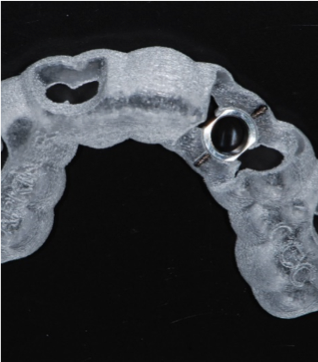

Fig 10. Surgical guide.

Figure 10

The CBCT and digital scan were placed in software to merge the two. Figure 8 shows the superimposition of the scan over the CBCT. The clinician used the volumetric data to determine implant size, depth, and position. The surgeon, dentist, and laboratory were all involved in a conference call to go through several different implants. They chose the implant size and length based on the position of the sinus, the width of the alveolus, and the appropriate position for an ideal surgical result.

These data were used to fabricate the surgical guide and a temporary. Figure 9 shows the implant in place digitally. All the data and models were taken into account before surgery. The clinician received a 3D-printed model with the tooth extracted, a guide (Figure 10), and a healing cap and temporary (Figure 11). The latter two were required for initial stability of the implant to immediately provisionalize. The "bail-out clause" is the healing cap because if the implant cannot be immediately loaded, the healing cap can be placed instead. For this case, the patient's tooth was extracted and bone had been grafted several months previously. Figure 12 shows the patient's previous tooth bonded into place. The flap was laid (Figure 13) and the surgeon was given a set of instructions that come with every guided case.